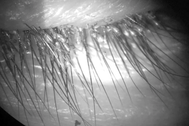

Hình ảnh rận ký sinh và đẻ trứng trên mi mắt nữ bệnh nhân (Ảnh: Nam Hải).

Soi mắt bệnh nhân dưới kính hiển vi, bác sĩ "ớn lạnh" khi phát hiện dưới lớp vảy là nhiều con rận mi bám chi chít trên mi mắt bệnh nhân. Trên lông mi, trứng rận xâu thành chuỗi.

Bác sĩ gắp nhiều con rận bám chặt vào mi mắt, xử lý hàng chục trứng rận trên lông mi, đồng thời hướng dẫn bệnh nhân cách vệ sinh mắt. Theo tiết lộ của nữ bệnh nhân, chị cũng có hiện tượng ngứa tương tự ở vùng kín.